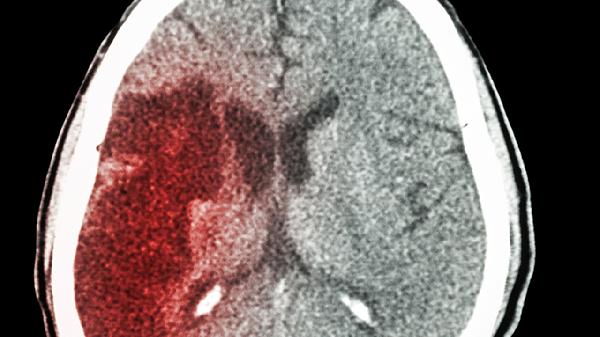

腦出血后遺癥癲癇可通過控制血壓、規(guī)律服藥、定期復(fù)查、避免誘因、康復(fù)訓(xùn)練等方式預(yù)防。腦出血后癲癇通常由腦血管損傷、神經(jīng)異常放電等因素引起,需結(jié)合藥物與生活方式干預(yù)降低發(fā)作風(fēng)險(xiǎn)。

每3-6個(gè)月需進(jìn)行腦電圖、頭顱CT或MRI檢查,評(píng)估腦組織恢復(fù)情況及癲癇灶活動(dòng)。通過影像學(xué)監(jiān)測(cè)可早期發(fā)現(xiàn)腦積水、軟化灶等并發(fā)癥,必要時(shí)聯(lián)合神經(jīng)外科會(huì)診調(diào)整治療策略。